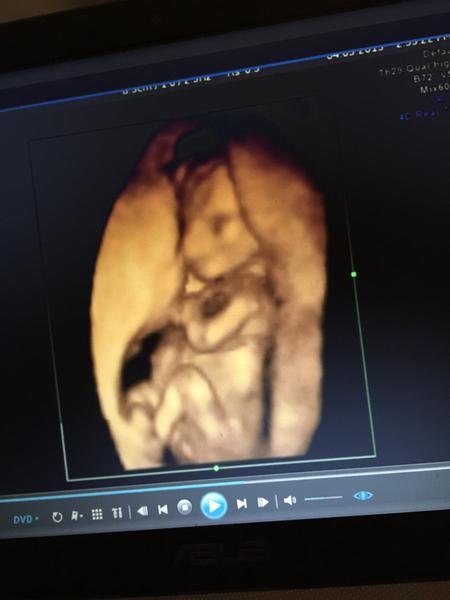

Dávalo mi o sobě velmi vědět cele těhu mám termín skoro za 14 dní a už mam strach jak mi bude dávat zabrat 😄

@babetka131 já bych řekla kluk :D

@deelayces dekuji prave doktori nam rekli jednou to a jednou to. Tak nevime co cekat🙂

@babetka131 já teda nevím ale já vidím kulišku :D no tak uvidíte :D